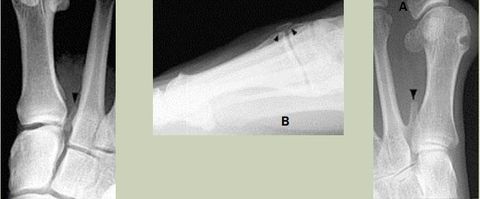

| What do the arrows show? | Stress fracture |

| Describe what has happened at the shaft of the 3rd met | Exuberant periosteal new bone production. May have resulted if a stress fracture was not treated and the patient continued weight bearing activities. |